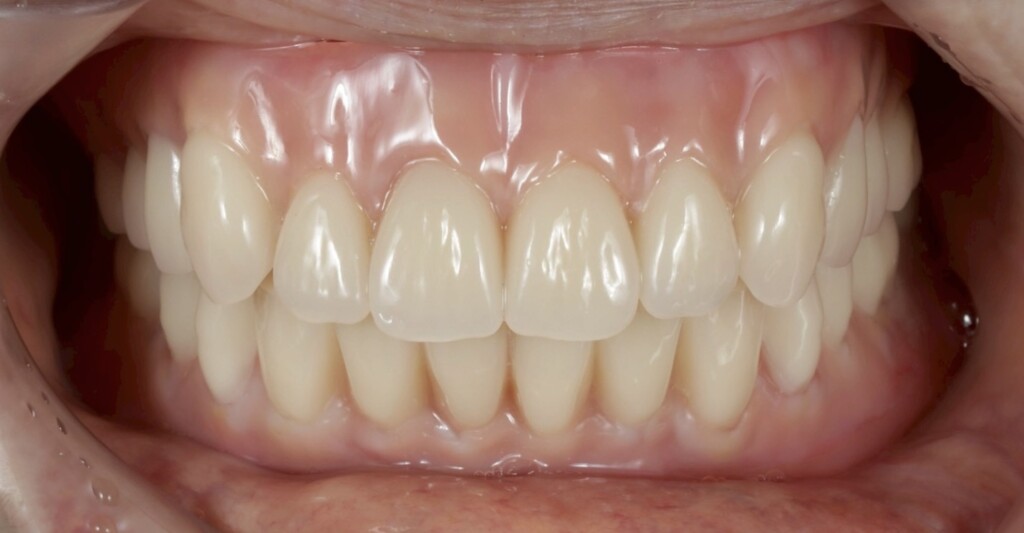

歯肉の質感まで再現された最終精密義歯

天然歯と見分けがつかない最終精密義歯

インプラントなしでも、ここまで動かない総義歯

- 真っ直ぐ噛んでも、横に歯を擦るように動かしても安定していることが左の動画で確認することができます

このように、

「いきなり完成させる」のではなく「仮の状態で確認しながら進める」

というプロセスを大切にすることで、見た目だけでなく、しっかり噛める機能の回復を目指しました。

最終的には、入れ歯の安定性が向上し、食事の際のズレや不安も軽減され、日常生活における「噛める」という機能を取り戻すことができました。

患者さんからは、

「不安な時期もあったが、今は治療して本当に良かった。今までで一番快適な入れ歯です」

というお言葉をいただき、大変嬉しく思っております。